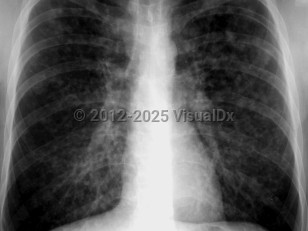

Chest pain, Pleural effusion, 50-59 year old Female

Pleural effusionPleural effusion